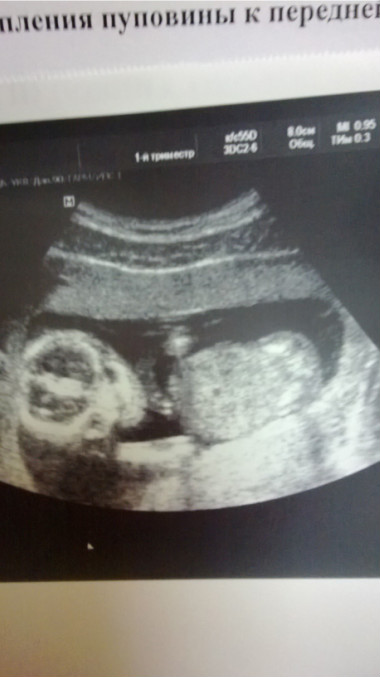

Были на узи в женской консультации! Что радует?) Сказали, что с ребеночком все хорошо! Огорчает?...то, что узи длилось 3 минуты и врач не сказала кто у нас мальчик или девочка, не показали мне малыша

Записалась на узи, будет в эту субботу! 3D Узи!!!)))) Так хочется увидеть мою маленькуую!!! Очень!!!

Здесь малышу 14 неделек 5 дней)))